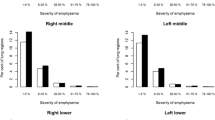

The variation in CT air trapping measures on repeat CT examinations is summarised in Figs. 3 and 4. As shown, the limits of agreement for the uncorrected quantitative CT air trapping measures were −15.0 to 11.7 % for EXP−856 and −9.8 % to 8.0 % for E/I-ratioMLD. After application of lung volume correction, this changed to −12.5 to 8.8 % (EXP−856, P = 0.12) and −7.5 to 5.8 % (E/I-ratioMLD, P = 0.17). In subjects with superior breath hold reproducibility, the limits of agreement were −10.7 to 7.5 % (EXP−856, P = 0.002) and −9.2 to 7.9 % (E/I-ratioMLD, P = 0.75).

Variation in CT air trapping (EXP−856) on repeat CT examinations. The left upper graph shows the uncorrected values for the complete group. The right upper graph shows the volume corrected values for the complete group. The lower graphs show the uncorrected values for subjects with inferior (left) and superior (right) breath hold reproducibility, defined as difference of expiratory lung volume outside or within the interquartile range around the mean, respectively. The x-axes show the means of CT air trapping measurements at both acquisitions, and the y-axes show the differences between the measurements. The solid lines represent the mean difference, whereas the dashed lines represent the limits of agreement

Variation in CT air trapping (E/I-ratioMLD) on repeat CT examinations The left upper graph shows the uncorrected values for the complete group. The right upper graph shows the volume corrected values for the complete group. The lower graphs show the uncorrected values for subjects with inferior (left) and superior (right) breath hold reproducibility, defined as difference between CT examinations of exhaled lung volume outside or within the interquartile range around the median, respectively. The x-axes show the means of CT air trapping measurements at both acquisitions, and the y-axes show the differences between the measurements. The solid lines represent the mean difference, whereas the dashed lines represent the limits of agreement

Regarding the longitudinal application of CT air trapping assessment, our results lead to the following considerations. First, uncorrected EXP−856 shows large variability on repeat CT examinations, whereas the variability is considerably less for uncorrected E/I-ratioMLD. Second, EXP−856 is more sensitive to the expiratory effort, which is illustrated by the significant difference in the limits of agreement between the subgroups with superior and inferior breath hold reproducibility on repeat CT examinations. Third, application of lung volume correction does not significantly narrow the limits of agreement of the CT air trapping measures. An interesting finding is that application of lung volume correction can create negative values for EXP−856, while it is expressed in percentages (see Table 3). This may well be explained by the fact that the volume correction method used assumes a simple linear relation [17, 18], which seemingly does not apply for expiratory analyses. Application of the volume correction method in E/I-ratioMLD, which combines inspiratory and expiratory data, does not encounter these difficulties. Taken together, our results suggest that E/I-ratioMLD is the preferred CT air trapping measure, because it shows the narrowest limits of agreement and is least dependent on variations in inspiratory and expiratory volume. Nevertheless, our main conclusion is that both CT air trapping measures may not be very suitable for longitudinal application, given the substantial variation between CT examinations regardless of good lung volume reproducibility or lung volume correction. Whether other lung volume correction methods or exact replication of lung volume by spirometric gating sufficiently improves variation between CT examinations requires further study.